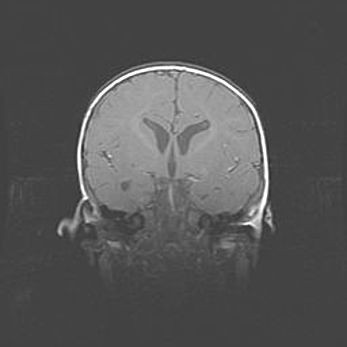

Сообщающаяся гидроцефалия. Кистозная энцефаломаляция головного мозга.

Возраст: 3 месяца 4 дня

Вес: 3100 г

Пол: женский

Окружность головы: 34 см

Срок гестации: 31 неделя

Кистозная энцефаломаляция головного мозга - одна из форм поражения головного мозга в детском возрасте. Характеризуется возникновением множественных и распространённых кист в коре, белом веществе и подкорковых образованиях головного мозга у плодов, новорождённых и детей раннего возраста. Развитие кистозной энцефаломаляции связано с внутриутробной асфиксией и гипотонией, родовой травмой, тромбозом синусов, пороками развития сосудов, инфекциями, сепсисом и другими причинами. Наиболее значимые инфекционные агенты: вирусы простого герпеса, цитомегалии, краснухи, токсоплазмы, энтеробактерии, золотистый стафилококк и другие.